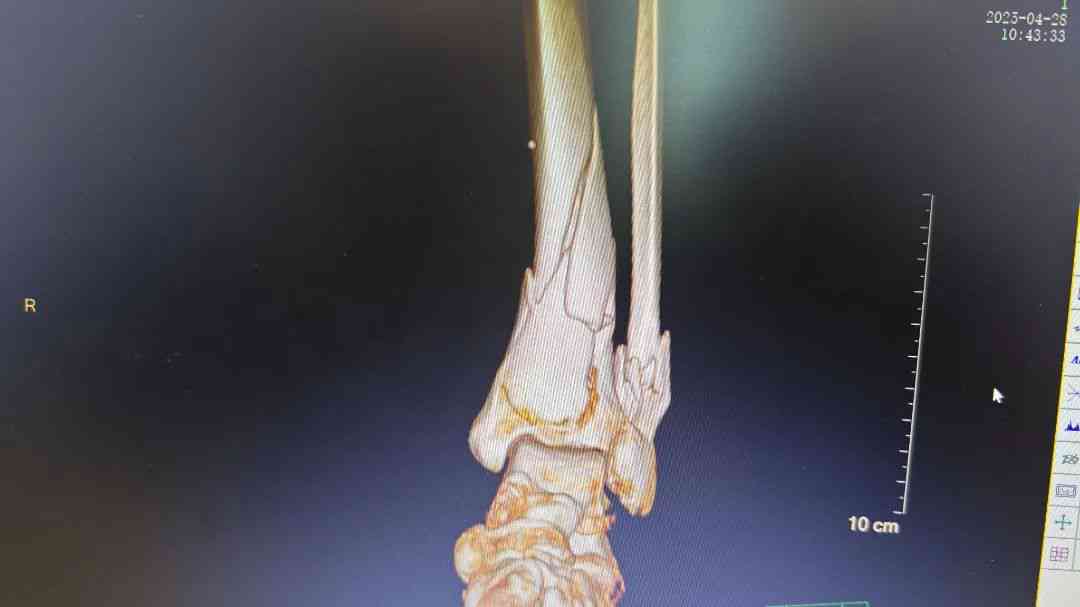

微信图片_20250512172753.jpg 微信图片_20250512172755.jpg 术前腿部影像

经过检查,发现李阿姨小腿明显畸形,骨折成角移位明显,CT显示左胫腓骨远端粉碎性骨折,右胸部7根肋骨骨折合并气胸。